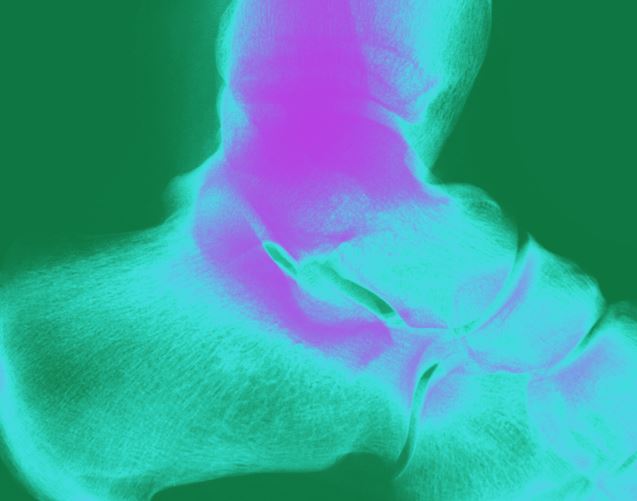

Nach einer Knöchelfraktur kann man sich die ein oder andere Bildgebung im Verlauf wohl sparen. Eine Studie zeigt: Das Röntgen jenseits der zweiten Woche bringt den Patienten über ein Jahr gesehen keinerlei Vorteil.

Das Sprunggelenk muss offenbar nach einer Fraktur weniger oft geröntgt werden als bisher praktiziert.